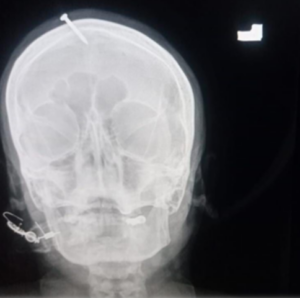

ଏକ୍ସ-ରେ ମହିଳାଙ୍କ କପାଳରେ ୫ ସେଣ୍ଟିମିଟର (ଦୁଇ ଇଞ୍ଚ) କଣ୍ଟା ପଶି ଥିବା ଦେଖିବାକୁ ପାଇଥିଲୁ। କିନ୍ତୁ ଏଥିଯୋଗୁ ତାଙ୍କ ବ୍ରେନରେ ଆଘାତ ଲାଗି ନ ଥିଲା। ହାର୍ମର କିମ୍ବା ତା’ ଭଳି କିଛି ଓଜନିଆ ଧାତୁରେ କଣ୍ଟାକୁ ମାଡ଼ କରାଯାଇଥିବା ଡାକ୍ତର ହାଇଦର ଖାନ କହିଛନ୍ତି।